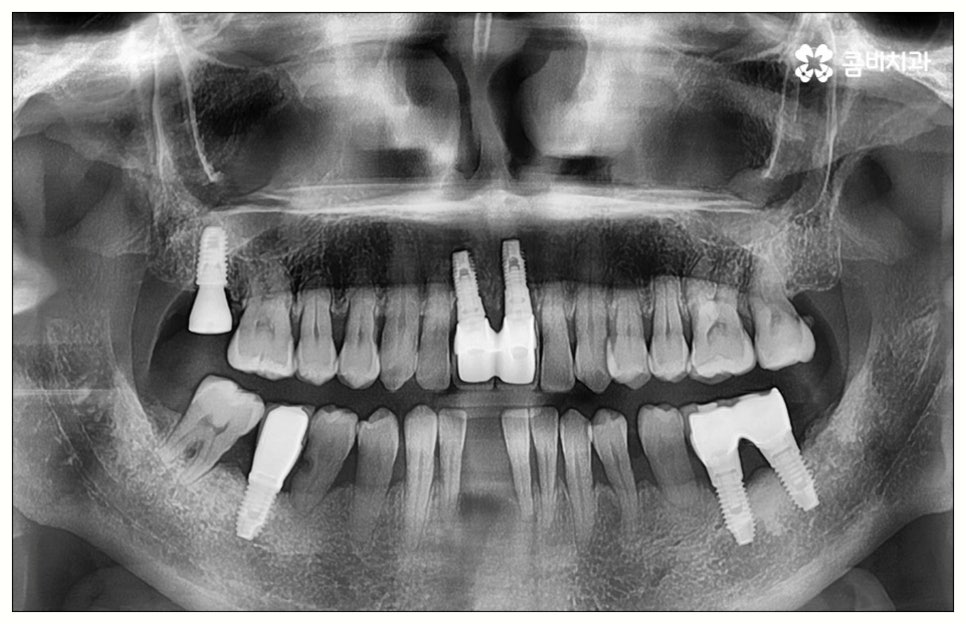

그러나 모든 환자분들이 원데이임플란트 방식을 이용할 수 있는 것은 아니기 때문에 주의하실 필요가 있어요. 말씀드렸던 것처럼 임플란트 수술은 직접 환자의 잇몸뼈에 식립을 진행하는 방식의 치료이기 때문에 잇몸뼈 상태가 양호하지 않은 분들의 경우 발치 후 바로 임플란트를 심는 것이 식립 성공률이나 지속적인 안정성 측면에서 좋지 않을 수 있어요. 특히 잇몸 질환으로 인해 염증이 심한 경우 또는 바탕이 되는 잇몸뼈의 밀도나 높이가 많이 부족한 경우에는 원데이임플란트 방식이 불가능하다고 할 수 있는데요.

이때 만약 무리하게 즉시 식립을 진행하게 되면 임플란트 치아가 제대로 기능하기 어려울 뿐 아니라 주위염 등 부작용을 일으킬 가능성이 높아 주변 잇몸 및 치아에도 좋지 않은 영향을 주게 되며 결국 임플란트가 흔들리거나 빠지면서 재수술이 필요한 상황까지 이를 수 있으므로 필요한 치료부터 선행하는 것이 좋을 거예요. 위에서 예로 든 상황이라면 잇몸 염증을 먼저 꼼꼼하게 치료한 후 또는 뼈이식술을 통해 안정성을 높인 후에 임플란트 식립을 진행하실 필요가 있어요. 이 과정에서 무엇보다 중요한 것은 수술 전 3D CT를 통해 환자의 상태를 정확하고 꼼꼼하게 확인하고, 환자의 연령, 치아를 상실하게 된 원인 및 시기, 식습관 등 관련된 모든 부분을 빠짐없이 검토하여 각자에게 꼭 맞는 계획을 세운 다음 회복 정도를 체크해 가면서 무리하지 않게 진행해 나가는 것이기 때문에 정밀 진단 장비 및 숙련된 의료진이 있는 치과에서 임플란트 치료를 받으시도록 권유드리고 있습니다.